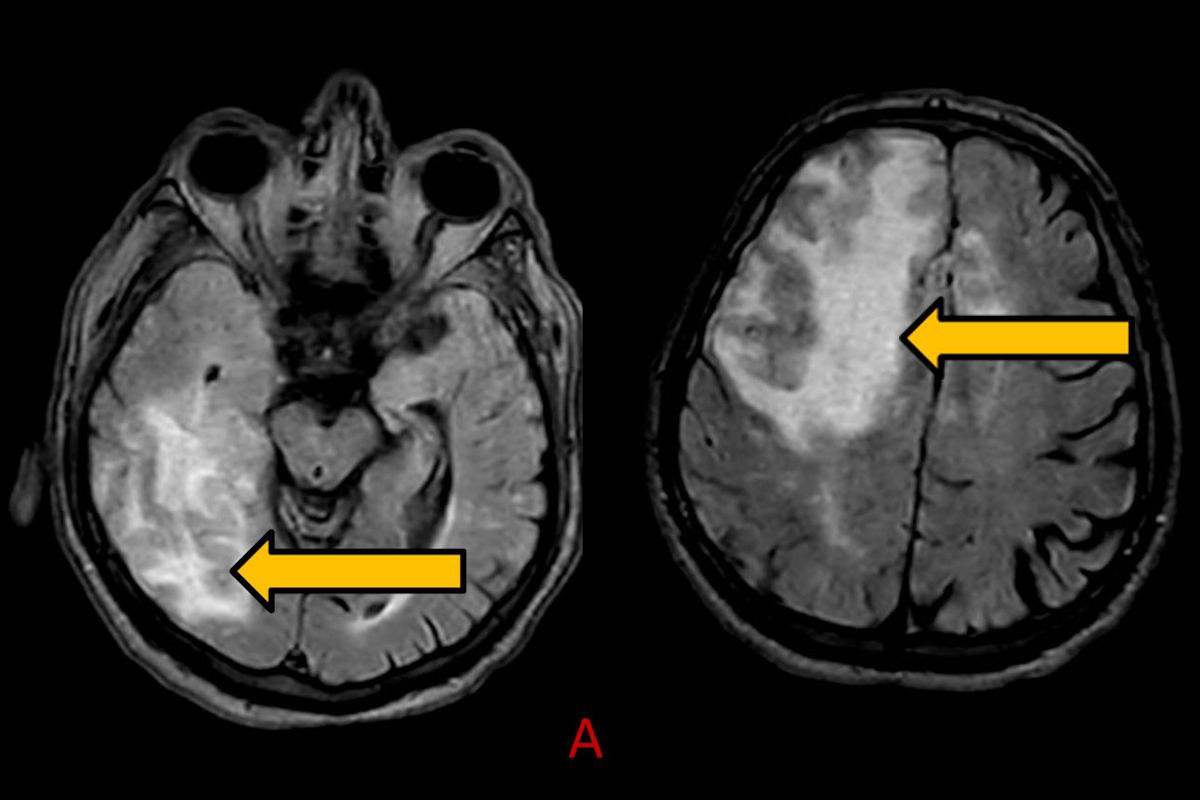

- A) Aksiyel planda FLAIR sekansta asimetrik kortiko-subkortikal vazojenik ödemi düşündüren yüksek sinyalli hafif ekspansil lezyonlar (turuncu ok).